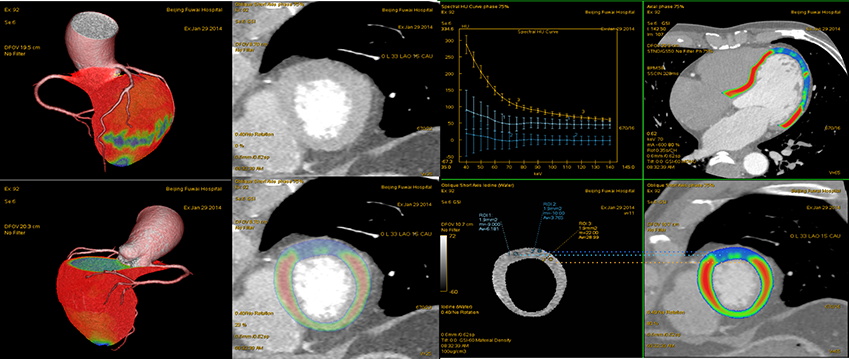

病例展示:心肌能谱灌注图像

左室短轴位对心肌缺血显示不敏感,能谱伪彩图清晰显示左室前间壁缺血区(蓝色区域),碘定量分别为:ROI 1:6.18(亮蓝,低密度缺血区);ROI 2:3.76(蓝色,更低密度缺血区);ROI 3:28.99(100ug/cm)(黄色,正常),与相应病变的冠脉供血区相一致

CT表现 左前降支近段软斑块,能谱示脂核形成 GSI Myocardium Perfusion:左室前间壁缺血